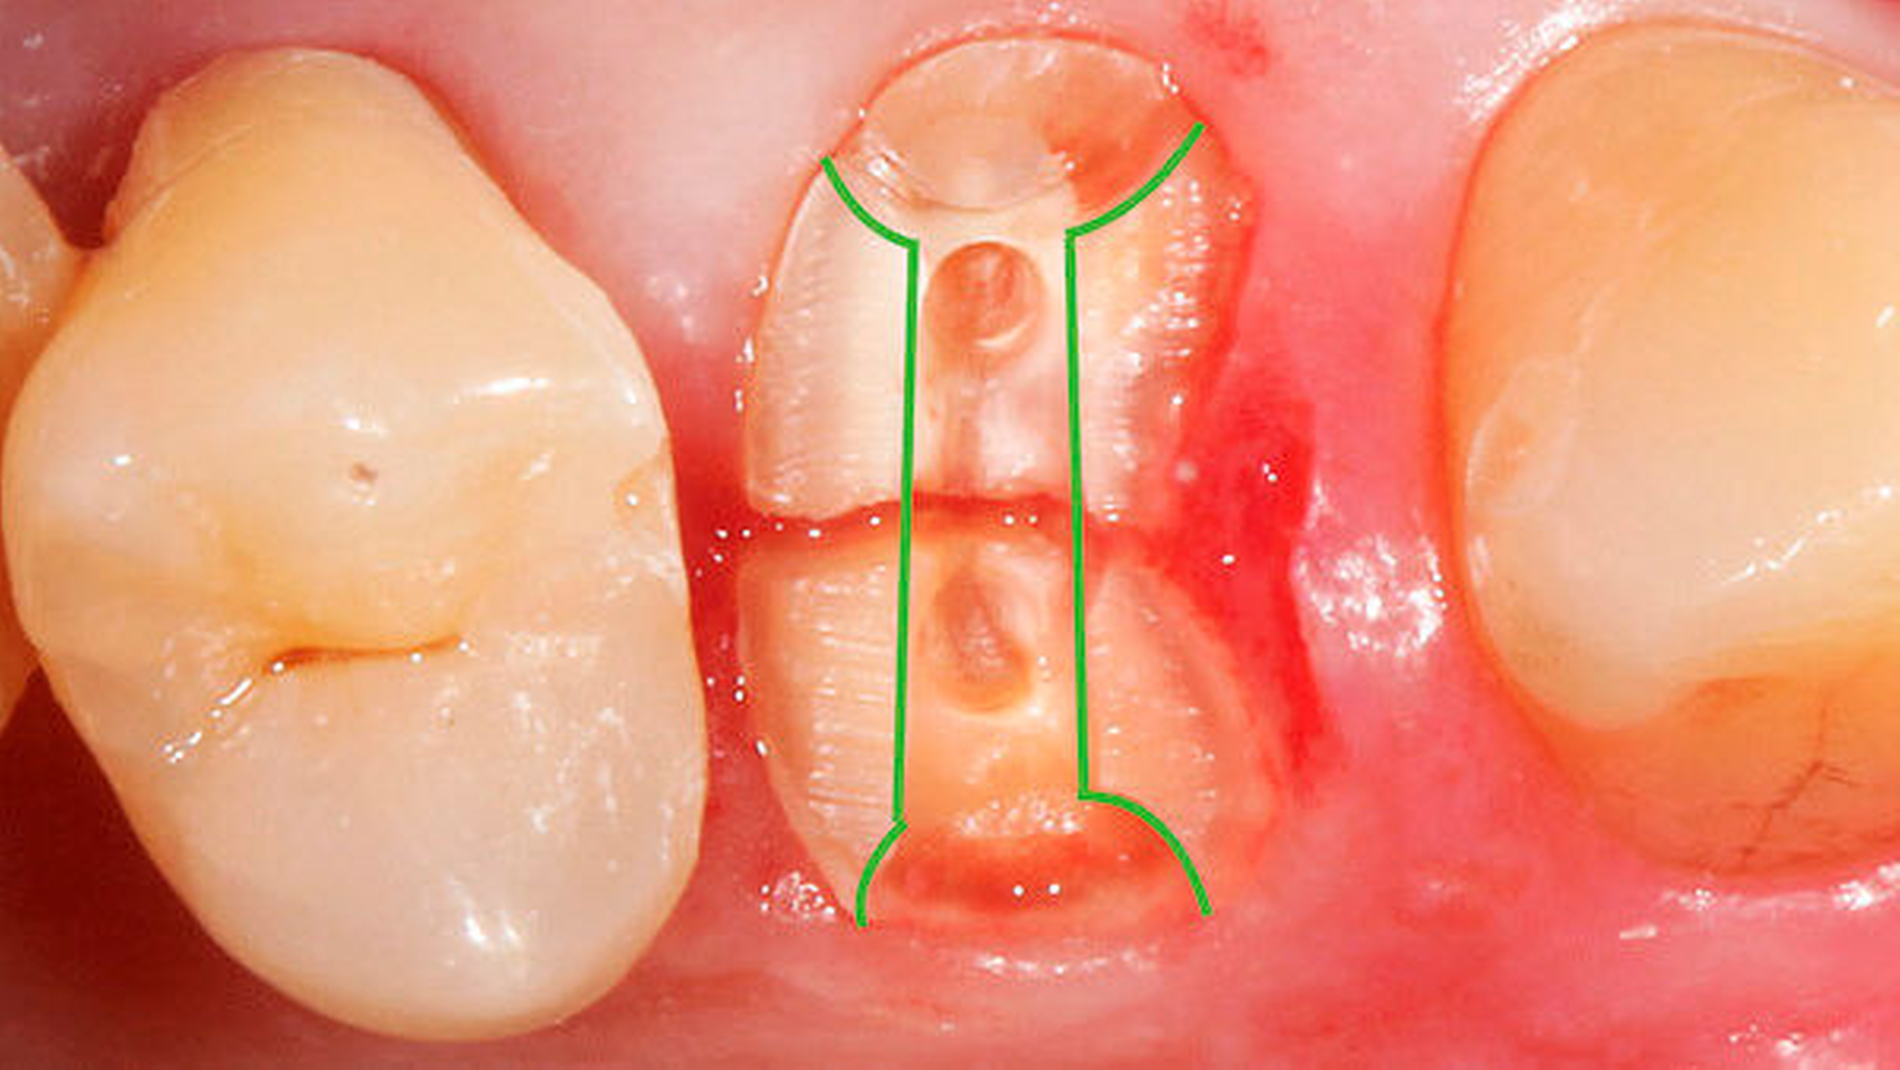

2 | Präparation einer Rille in bukkooraler Richtung zur Positionierung der Extrusionshantel (Fa. Komet) (Abb. 2) |

3 | Adhäsive Fixierung der Extrusionshantel in der Rille (Abb. 3) |

4 | An einem Ende der Extrusionshantel ist bereits eine Retentionslinse angebracht. die zweite Linse muss am gegenüberliegenden Ende adhäsiv fixiert werden |

6 | Adhäsive Fixierung des koronalen 1/3 der ursprünglichen Krone (Frontzahnbereich. Abb. 3) oder der Extrusionsstege (Klammerdraht oder Extrusionssteg Fa. Komet) an den Nachbarzähnen |

7 | Das Extrusionsgummi wird von der oralen Retentionslinse zur vestibulären Linse gespannt (Abb. 3) |